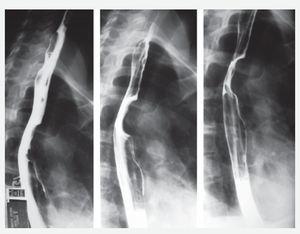

Mujer de 34 años sin antecedentes personales patológicos, quien consulta con historia de 3 meses de evolución de disfagia progresiva. Estudio baritado esofágico reveló compresión extrínseca en tercio medio (Imagen 1). La endoscopia alta mostró una lesión que ocluía 50% de la luz esofágica con mucosa intacta. La tomografía axial computada con contraste esofágico reveló una lesión intramural, no adherida a planos adyacentes a nivel de la pared esofágica lateral derecha en el tercio medio, cercano al cayado aórtico (Imagen 2). A la paciente se le realizó enucleación toracoscópica con abordaje lateral derecho de tumoración esofágica en tercio medio sin complicaciones (Fotos 1 y 2). El informe histopatológico reportó GIST (Gastrointestinal Stromal Tumor) esofágico CD117 (+). Estudio contrastado de control sin estrecheces ni escape. Fue dada de alta al cuarto día posoperatorio.

Imagen 2. TAC de esófago con contraste. Lesión intramural.